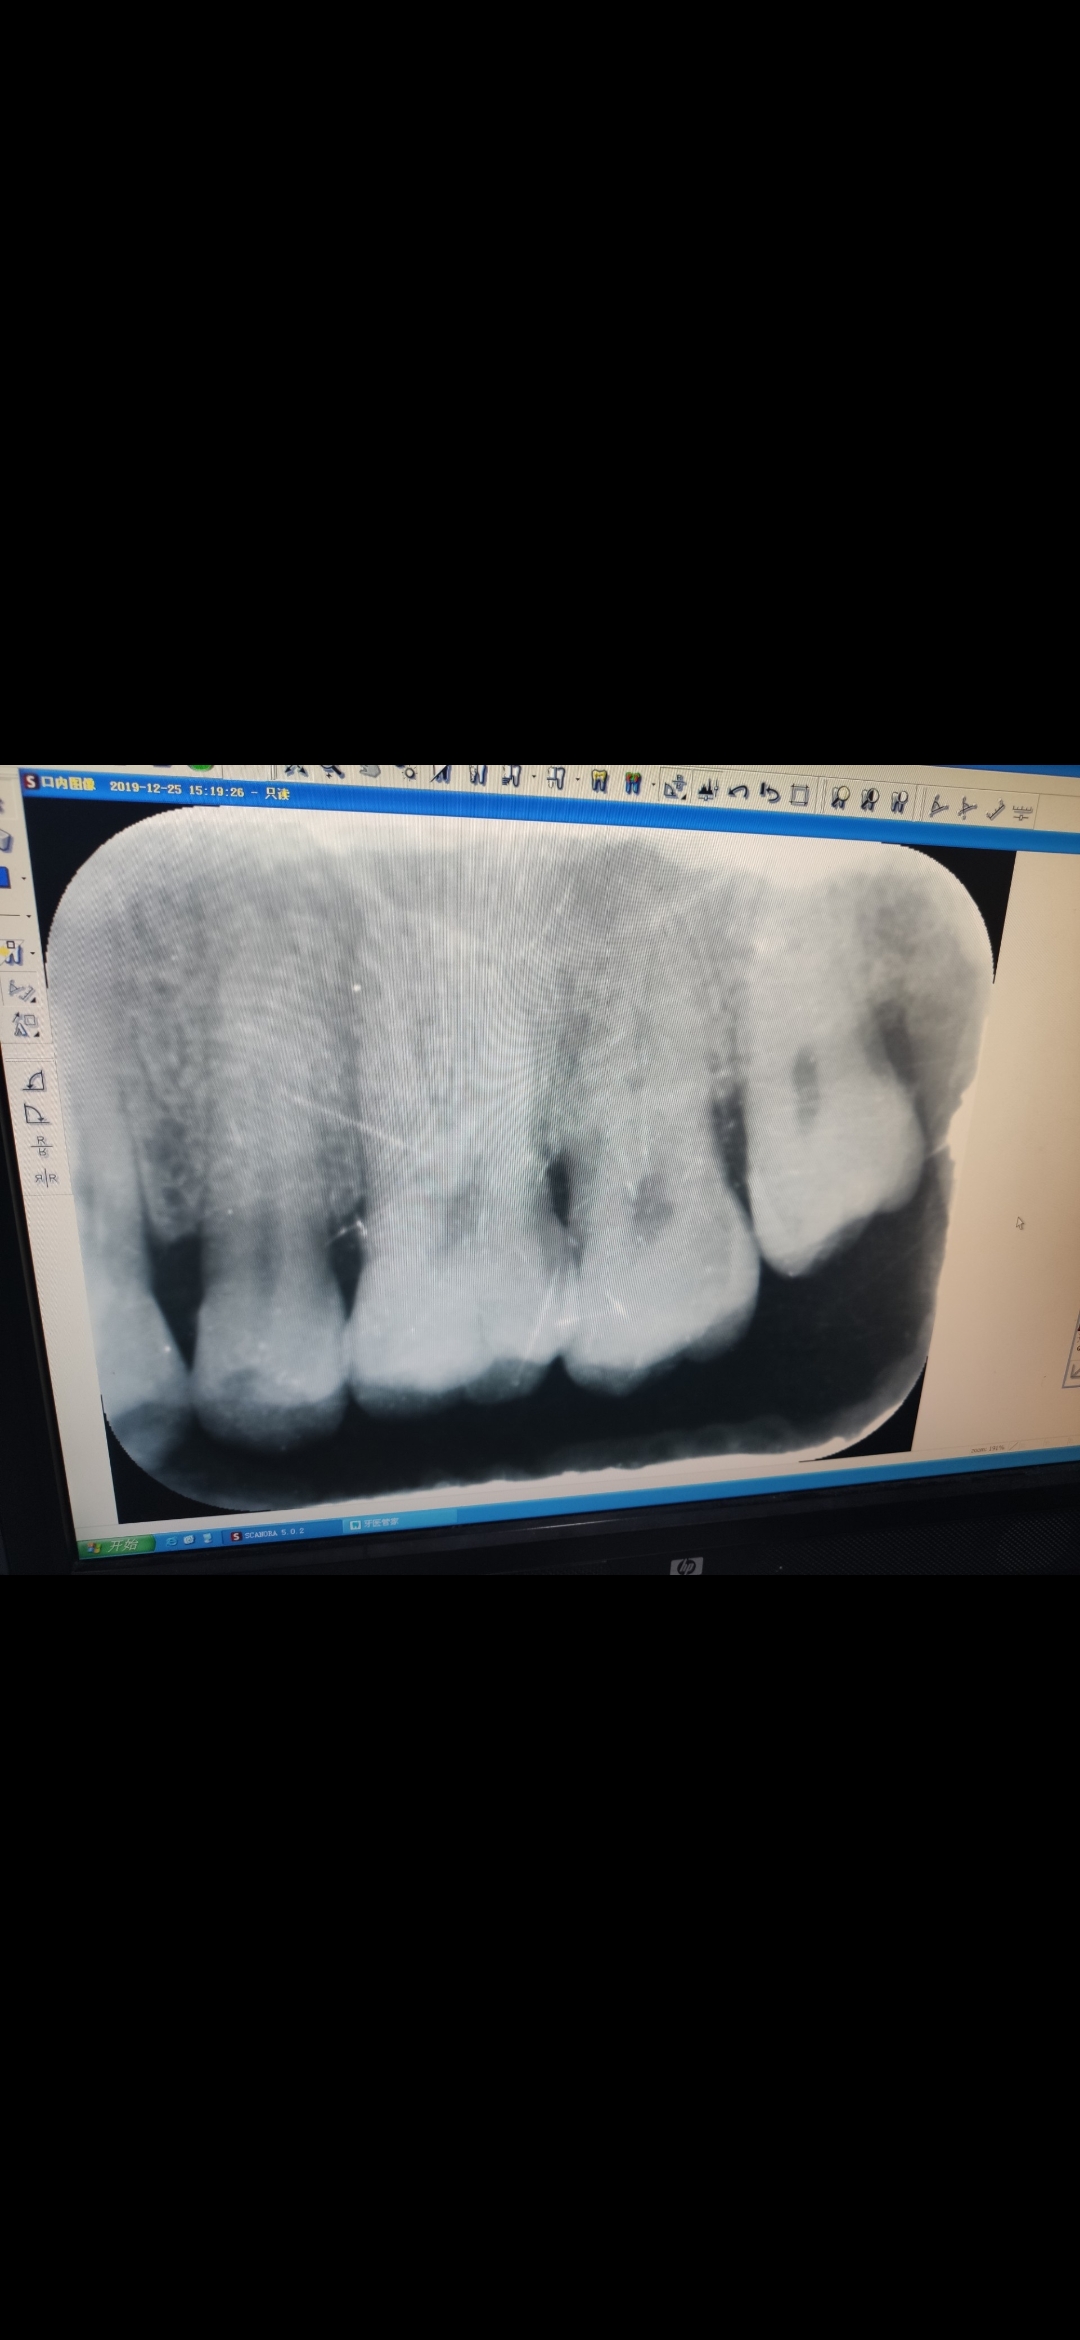

RVG是口腔科应用最广的检查手段,也是最常用的,

因为它在牙科治疗前、治疗中和治疗后都有助于诊断和治疗。临床上,利用牙片对牙齿硬组织病变、牙髓病变、根尖周病变及牙周病进行诊断治疗。